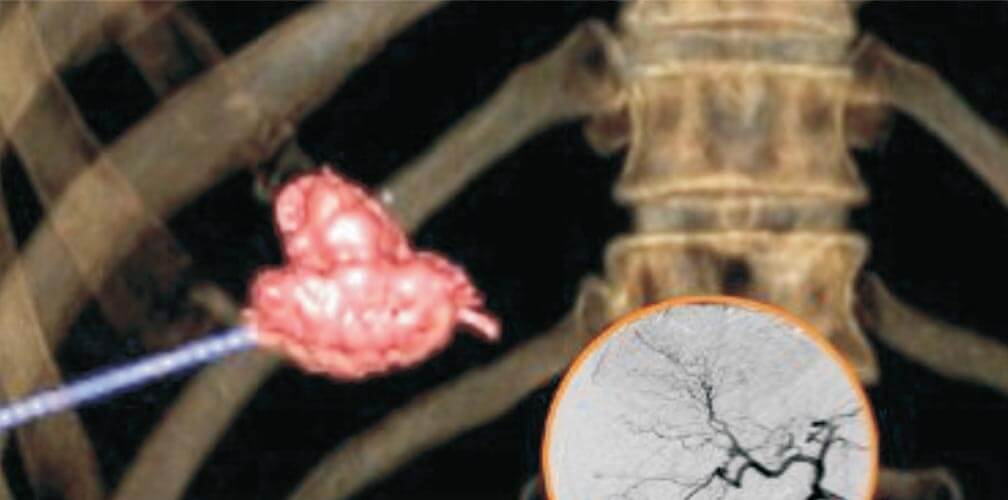

Intracranial AV malformations and AV fistulae are high flow vascular lesions in the brain. They can present with hemorrhage, headache, seizures, focal neurological deficit. Endovascular embolisation by Onyx is being used for either complete occlusion or size reduction of the AVM before microsurgery or radio surgery. Dural AV fistulaes are a specific condition seen as a sequelae to chronic dural venous sinus occlusion. Again, endovascular onyx embolisation is the treatment of choice in most of the dural AVFs. Carotico- cavernous fistulae is a specific type of AV fistulae seen around the cavernous sinus, mostly post traumatic. Patients with carotico cavernous fistula present with pulasatile proptosis, congestion of the eye and tinnitus. Endovascular balloon/coil occlusion is the treatment of choice in carotico cavernous fistulae.

With the team approach, comprising the Neurosurgeons, Neurologists, Interventionist and Intensivist, an efficient evaluation, pretreatment and post treatment protocols have been established in the management of subarachnoid haemorrhage, acute ischemic stroke, hemorrhagic stroke, chronic ischemic cerebrovascular disease. With this disease specific management paradigms focusing not only on procedural outcomes but also on post procedural neurocritical care management and rehabilitation, we are able to obtain optimum results even in the most dreaded neuro vascular diseases like subarachnoid haemorrhage due to ruptured aneurysms. So far, we have done a total of about 200 neuro vascular procedures which includes about 80 cases of advanced neurointerventions,including flow diverter placement for intracranial aneurysms, stent assisted coiling, stentrieval for large vessel occlusions, onyx embolisation for intracranial pail AVMs and dural AVFs. With the comphrensive team approach, we are able to achieve clinical outcomes in various disease categories on par with those described in the literature and state of the art centres across the world.